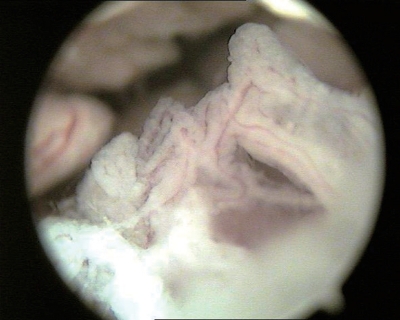

①子宫颈管:呈圆形或椭圆形管筒,黏膜呈泛白、淡红或红色,可见较深的纵行皱襞(图3-2)。